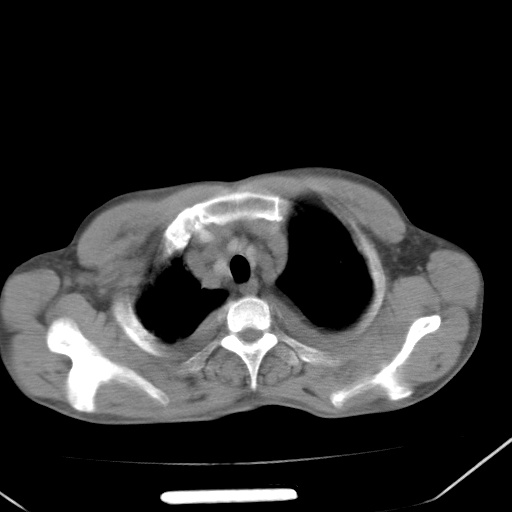

男、42岁、咯血3天。既往有甲亢、贫血、血尿蛋白尿史多年。血象:wbc:6.   中性粒:70.6%。

双肺野对称性磨玻璃影,分布于内中带,双侧胸水,患者有咯血。

双肺野广泛对称性磨玻璃影、实变影,以肺门为中心,主要分布于内中带,符合典型肺泡性肺水肿;伴双侧胸腔少量游离积液。结合患者既往病史且咯血就诊,支持多因素(尿毒症等)所致之肺水肿、肺出血、胸水;影像表现暂不考虑心源性水肿,且症状也不太符。需密切随诊结合临床治疗等进一步明确。

心影增大密度略低,双肺磨玻璃样高密度影及双侧胸腔积液,考虑心功能不全继发双肺肺水肿及双侧胸腔积液。心影密度略低,考虑贫血所致。